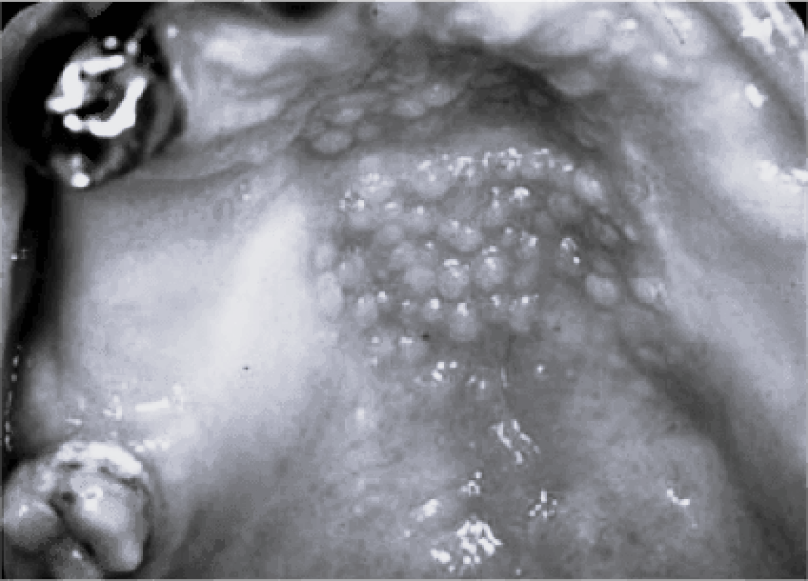

Các tuýp HPV nguy cơ cao gây ung thư bao gồm 16, 18, 31, 33, 45, 52, 58…, trong đó phổ biến nhất là tuýp 16 và 18. Ảnh: Journaldesfemmes.

Tăng sản dạng nhú viêm do HPV. Ảnh: BSCC.